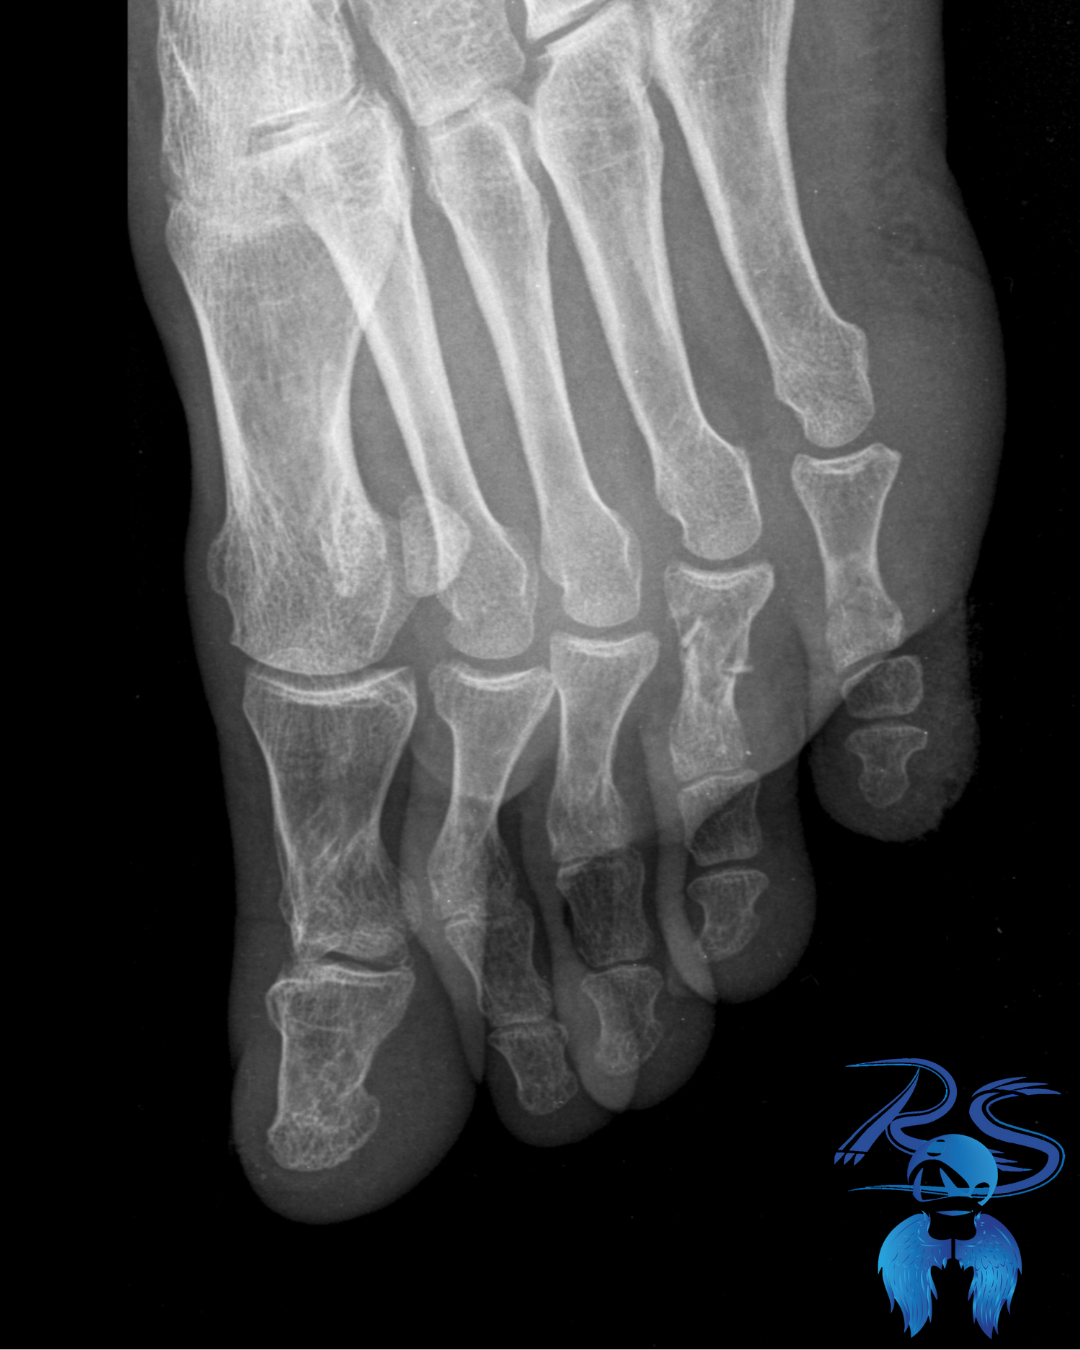

Flexores de los dedos: tensión acumulada

Los dedos comprimidos por zapatos estrechos permanecen en contracción constante.

Dolor en la base de los dedos

Cómo ayuda el masaje terapéutico: La movilización dedo por dedo libera los puntos gatillo y mejora la función del pie al caminar.

Fascia plantar: la base del dolor en el pie

La fascia plantar sostiene el arco del pie. Cuando el calzado limita el movimiento natural, esta zona se sobrecarga.

Cómo ayuda el masaje terapéutico: La liberación miofascial y la presión profunda reducen la inflamación, mejoran la circulación y devuelven elasticidad al tejido.